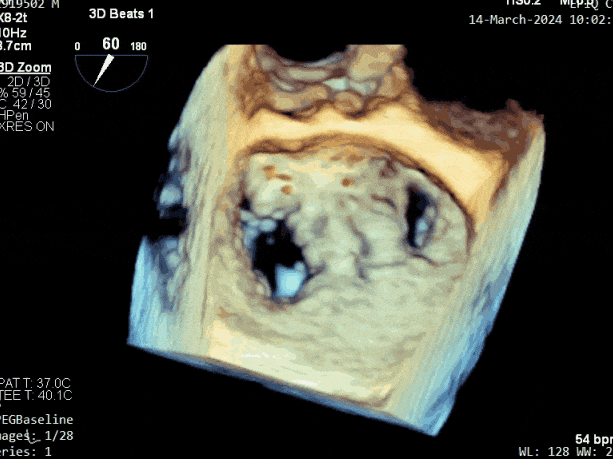

第三个瓣膜夹释放后评估,释放后评估,二尖瓣呈双孔,组织桥张力合适,瓣膜夹轴向与二尖瓣闭合线垂直,无残余反流

肺静脉血流频谱恢复为收缩期正向